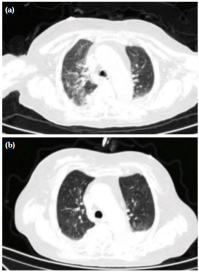

After admission, the patient underwent seven sessions of continuous renal replacement therapy (CRRT), six sessions of plasma exchange (PE), four sessions of intermittent hemodialysis (IHD), imipenem and cilastatin sodium for anti-infection, voriconazole as antifungal, methylprednisolone 40 mg once daily intravenous infusion, and cyclophosphamide 0.6 g intravenous infusion. On Day 4 of admission, the patient had hemorrhagic spots on the nose and white spots on the tongue (Figure 1a). Nasal bleeding was significantly reduced after the second plasmapheresis (Figure 1b). After the fifth plasmapheresis, the nose swelling and bleeding disappeared (Figure 1c). On Day 26 of admission, the urine volume was 3,000 mL within 24 h, and renal function recovered and improved after examination. After six plasmapheresis sessions, thoracic CT exudation decreased significantly (Figure 2). On Day 29 of hospitalization, the patient was discharged with complete improvement, urine volume returned to normal, blood creatinine decreased to 132 µmol/L, and blood culture test result was negative. At a later follow-up, a moderate dose of prednisone (30 mg, gradually reduced to 5 to 10 mg for maintenance) was administered orally combined with cyclophosphamide monthly (0.8 to 1.0 g each time, 6 to 8 g in total) and intravenous drip shock therapy was administered to maintain immunosuppression. No obvious signs of disease were observed.

Granulomatosis with polyangiitis can be characterized by saddle nose deformity, septal perforation-saddle nose deformity, pulmonary nodules, orbital masses, dacryocystitis, and ventricular septal perforation.[2,3] The case reported in the present study was mainly characterized by nasal swelling and mucosal bleeding. Thoracic CT of the patient showed exudative lesions in both lungs upon admission, and broad-spectrum antibiotics were actively administered at the initial admission stage; however, the antibacterial treatment was ineffective. The inflammatory reaction on thoracic CT increased after the examination, as hormone and plasmapheresis were effective and the exudative lesions of the patient's lungs were considered to be caused by granulomatous polyvasculitis.